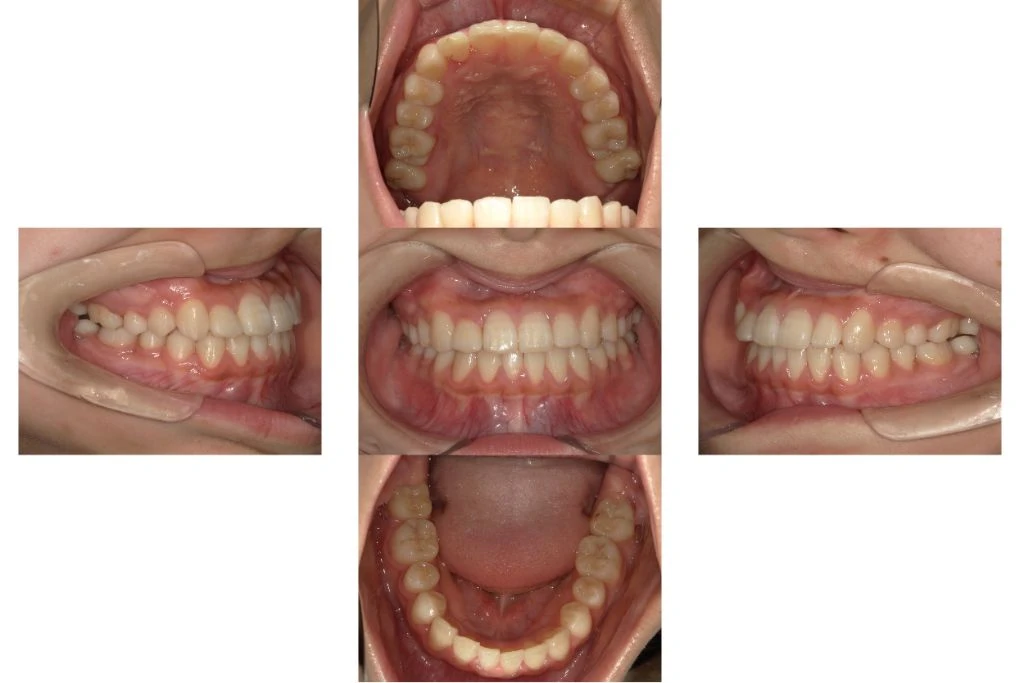

【治療後】

MSEを併用しながらワイヤー矯正が終了した状態です。本来の顎位で上下の正中(真ん中)が合ってきて概ね矯正治療としてのゴールが見えてきました。